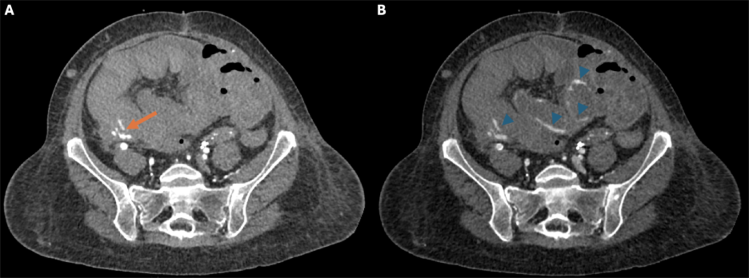

The presence of an associated arterio-enteric fistula was confirmed with early arterial phase imaging, demonstrating contrast within the bowel lumen with associated pooling on delayed images (Figure 2). The patient’s lactate was elevated at 4.4 mmol/L, and her hemoglobin had decreased from a baseline of 9.4 to 7.0 g/dL.

Figure 2. (A) Arterial phase axial image just inferior to the pseudoaneurysm shows active contrast extravasation (arrow) into a blood-filled right lower quadrant bowel loop. (B) Delayed image reveals pooling of contrast (arrowheads) as fresh blood surrounds hematoma filled loops of bowel.